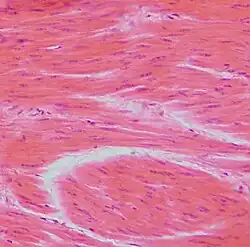

In der Histologie werden Gewebeproben untersucht. Dazu werden mikrometerdünne, gefärbte Gewebsschnitte hergestellt und am Lichtmikroskop beurteilt. Die elektronenmikroskopische Untersuchung von wesentlich dünneren Schnitten (0,01–0,5 µm) fällt vorwiegend in den Forschungsbereich.

Die Verarbeitung von Formaldehyd-fixiertem, Paraffin-eingebettetem Gewebe inklusive der Hämatoxylin-Eosin-Färbung stellt die weltweite Routine-Methode der Pathologie dar und dauert durchschnittlich ein bis zwei Tage von der Probenannahme bis zur Befundung. Im Gegensatz zum klinisch-chemischen Labor sind viele Arbeitsschritte von Hand durchzuführen. Besonders die Schnittherstellung am Mikrotom bedarf großen Geschicks.

Es gibt eine Unzahl verschiedener histologischer Färbungen, die im Laufe der letzten 120 Jahre entwickelt wurden. Der Großteil stammt aus den ersten 30 Jahren des vorigen Jahrhunderts. Im modernen Histolabor hat sich eine überschaubare Anzahl an Färbungen durchgesetzt. An erster Stelle steht die Hämatoxylin-Eosin-Färbung (HE-Färbung) als Routine- und Übersichtsfärbung. Dafür werden meist computergesteuerte Färbeautomaten eingesetzt. Daneben werden für bestimmte Fragestellungen sogenannte Spezialfärbungen (meist von Hand) durchgeführt.